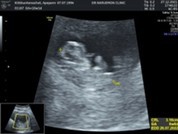

ขยับแขนขยับขาแล้วค่ะ❤️

Post reply image